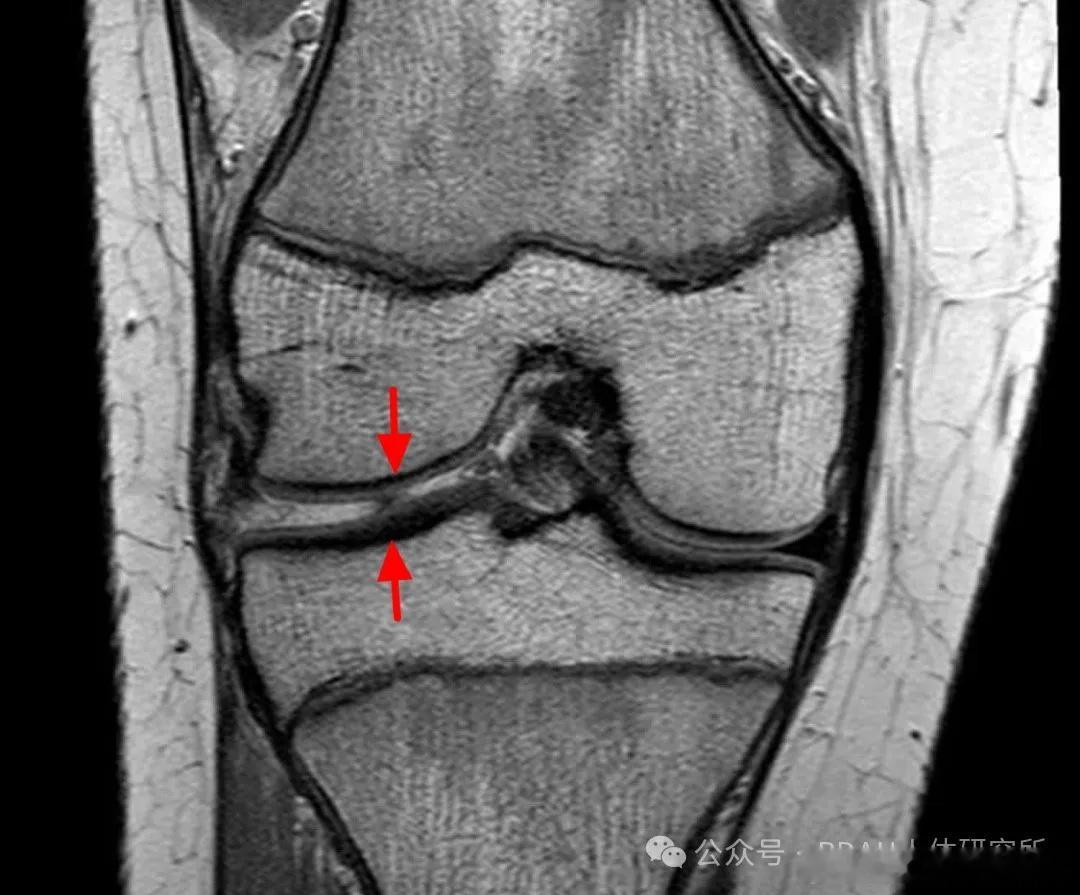

膝关节损伤 【半月板损伤】半月板伤了,手术or保守,该怎么康复?今天就来聊一聊——【半月板的功能】✅稳定膝关节、传递应力、协助润滑关节——半月板由2个纤维软骨板构成呈"C"字型,外缘厚,内缘薄 图1,紧密附着在胫骨平台中部的髁间结节处 图2。——胫股关节是一个完全不吻合曲面,通过膝关节的应力集中在很小的面积上,有了半月板,关节接触面积增大,应力就不会过于集中,关节稳定性也会增强。因此在切除半月板时,应尽量地保存未遭损伤的半月板,从而最大可能地保留半月板的功能。【半月板损伤机制】⚠️扭转——当膝关节处于屈曲位、而胫骨固定时股骨下端由于外力骤然过度内旋、伸直,可导致内侧半月板撕裂,或者股骨下端骤然外旋、伸直外侧半月板也可发生破裂; ⚠️压力——起跳或高处落下时,如果人体的缓冲技术不到位/膝关节压力过大也可能造成半月板撕裂;⚠️膝关节急速扭转,又受到横向外力——也易造成半月板撕裂同时可能并发膝关节前交叉韧带撕裂或断裂。而由于半月板的运动机制,内侧半月板破裂的机会比外侧半月板多7-10倍。【保守治疗】①半月板是在血供丰富区的撕裂(外侧血供比内侧丰富);②撕裂不要超过2cm长度;③膝关节要带夹板限制活动6周;④根据半月板缝合的情况进行康复;⑤急性伤。如果是处于急性损伤,就需要遵循RICE原则:制动、冰敷、加压、抬高。半月板康复健闻登顶计划